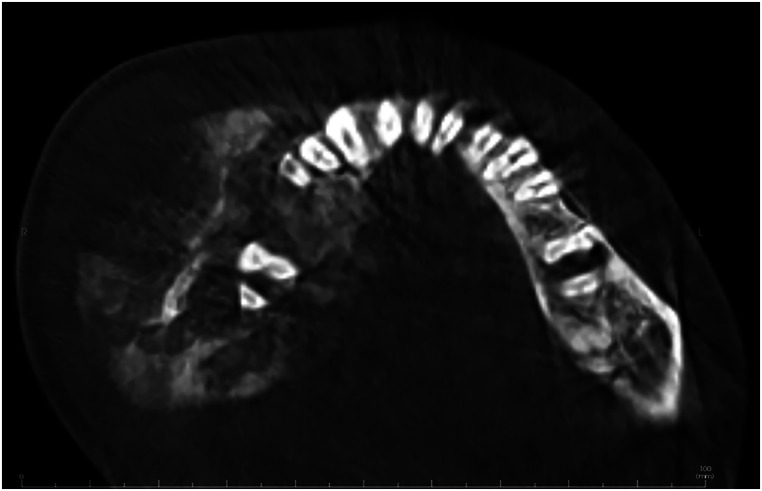

Jaw osteosarcoma (JOS) is a rare, distinct variant that differ from long bone osteosarcoma (LBOS) in several aspects. JOS typically appears about twenty years later than LBOS, displays a lower propensity for metastasis to other organs, and exhibits better survival rates. The dissimilarities in clinical and biological behavior between JOS and LBOS are likely due, at least in part, to variations in their respective microenvironments. In this report, we present a case of OS affecting the mandible in a young patient. This case displayed classic radiographic features but a unique histopathological presentation, posing a diagnostic challenge for pathologists, especially if encountered in small biopsies.

Abstract Image